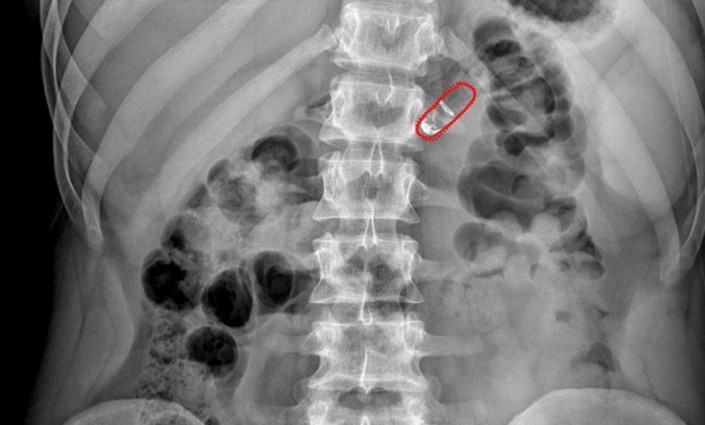

Индийские разработчики тестируют "умную капсулу" RaniPill для инъекций без шприца и боли в стенку кишечника, передает Tengrinews.kz со ссылкой на научный журнал IEEE Spectrum.

Прототип устройства успешно прошел испытания на людях. Новый проект представил известный индийский изобретатель медицинских инструментов Мир Имран (Mir Imran), создатель имплантируемого дефибриллятора. На разработку "умной капсулы" RaniPill команда Имрана потратила 7 лет.

После проглатывания миниатюрного устройства в кислой среде желудка растворяются его оболочки. В результате этого два химических вещества смешиваются в специальной микроемкости и выделяется небольшое количество углекислого газа, который надувает крошечную упругую сферу, как воздушный шарик. И под ее давлением из капсулы выдвигаются иглы, которые инъецируют препарат в стенку кишечника.

Она не содержит болевых рецепторов, зато густо пронизана сетью сосудов, куда тут же попадает лекарство. Так же растворяются и остальные части капсулы вместе с иглами, сделанными из биоразлагаемого полимера, а некоторые части выходят позже с переваренной пищей. Разработчики показали, что использование RaniPill не вызывает проблем при проглатывании, прохождении по пищеварительному тракту и даже при раздувании "шарика" и срабатывании иголок.

Были проведены испытания с примерно сотней подопытных животных и различными потенциально полезными препаратами, включая инсулин. Успешно закончились и тесты на 20 людях, хотя в этом случае команда Имрана пока обошлась без препаратов, лишь проверив ощущения добровольцев от применения "умной капсулы". Никакой боли от такого скрытого укола они действительно не почувствовали.

Для следующей версии капсулы RaniPill Имран и его команда разрабатывают крошечные беспроводные датчики для той части баллона, которая вдавливает микроиглу в стенку кишечника. При применении датчики могут отправлять беспроводной сигнал о том, что лекарство доставлено, что позволяет врачам отслеживать соблюдение пациентом режима лечения и получать текстовое сообщение, если пациент пропустил прием дозы.